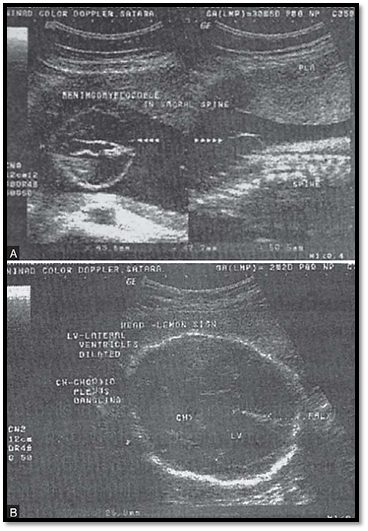

talipus. The condition is invariably fatal. Similarly in spina bifida, blockage in the normal CSF flow can result in hydocephalus (Figs 16.6A and B).

Figs 6A and B: Ultrasound showing. (A) Meningomyelocele and (B) Hydrocephalus occurring secondary to obstruction of the flow of cerebrospinal fluid,an example of a sequence